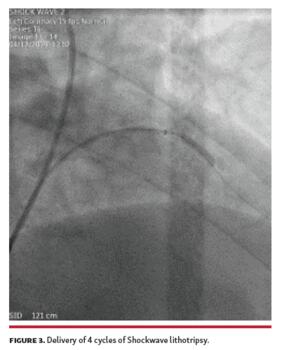

After several attempts with 2.0 x 15 mm and 2.5 x 15 mm compliant and non-compliant balloons used for predilation, a significant residual stenosis remained (Figure 2). At that time, we decided to use Shockwave intravascular lithotripsy (IVL; Shockwave Medical). A 3.00 x 12 mm lithotripsy balloon was chosen, but proved too bulky to advance and deliver. Guide-extension catheter improved support, and 4 cycles of lithotripsy were delivered, achieving full expansion (Figure 3). Subsequently, a 3.0 x 24 mm drug-eluting stent was delivered and deployed, with an optimal result (Figure 4).